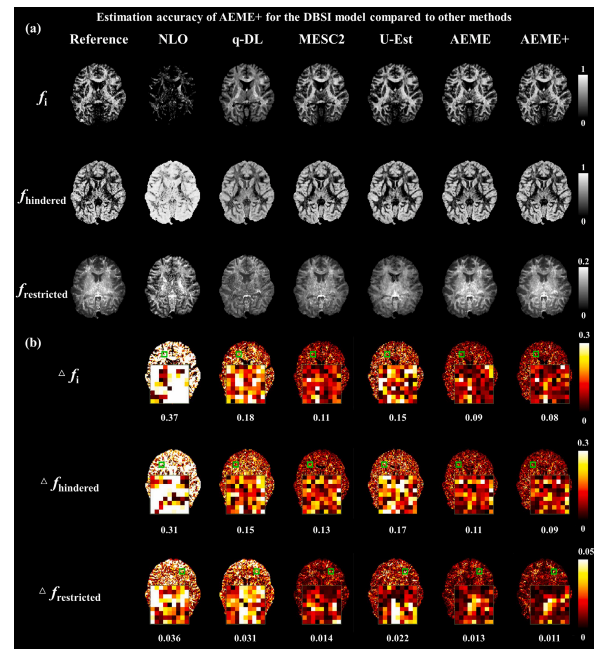

Fig. 5. Estimation accuracy of AEME+ for the DBSI model compared to other methods. (a) The reference and estimated DBSI parameters 𝑓𝑖 , 𝑓ℎ𝑖𝑛𝑑𝑒𝑟𝑒𝑑 , and 𝑓**𝑟𝑒𝑠𝑡𝑟𝑖𝑐𝑡𝑒𝑑 based on NLO,q-DL, MESC2, U-Est, AEME, and AEME+ in a test subject in DatasetMGH-3T (32 diffusion directions per shell at b-values of 1 and 3 ms∕μm2 ). (b) Estimation errors and zoom-inviews of 𝑓𝑖 , 𝑓ℎ𝑖𝑛𝑑𝑒𝑟𝑒𝑑 , and 𝑓𝑟𝑒𝑠𝑡𝑟𝑖𝑐𝑡𝑒𝑑 using NLO, q-DL, MESC2, U-Est, AEME, and AEME+ in a test subject in DatasetMGH-3T. The mean errors of the zoomed regions were marked.

图5:与其他方法相比,AEME+对扩散基谱成像(DBSI)模型的估计准确性。(a) 在数据集MGH-3T(每个壳层在(b)值为(1)和(3) (ms/μm2)时各有(32)个扩散方向)上的一个测试对象中,基于非线性优化(NLO)、(q)空间深度学习((q-DL))、MESC2、U-Est、AEME和AEME+所得到的参考值以及估计的DBSI参数各向异性信号分数((f_i))、受阻各向同性扩散分数((f{hindered}))和受限各向同性扩散分数((f{restricted}))。(b) 在数据集MGH-3T上的一个测试对象中,使用NLO、(q-DL)、MESC2、U-Est、AEME和AEME+对(f_i)、(f{hindered})和(f{restricted})的估计误差以及放大视图。放大区域的平均误差已做标记。